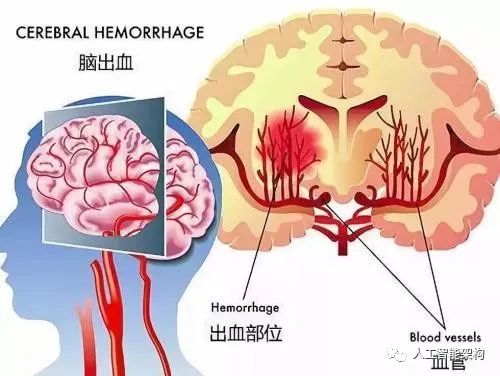

人工智能可以变得像放射科医生一样好,并有助于照顾脑出血患者吗?答案是肯定的。对脑出血的时间诊断是非常关键的,早期发现可以显着增加生存机会。可能存在一些无法及时诊断的情况,在这种情况下,AI能够提供帮助。我们训练一个深度神经网络成为“第二对眼睛”,并且它不用休息。

头部受伤或任何其他可导致脑出血的情况都很严重,需要尽快发现。优选的诊断方法是计算机断层扫描(CT)扫描。CT扫描足够详细(尽管不像MRI那么详细),用它们对患者进行成像(MRI更慢)的速度更快。NCCT扫描(非对比CT)扫描头部并通过提供大脑的3D图来检测脑出血,其中大脑可被视为2D切片序列。医生通常在这些切片序列中上下滚动以定位异常。